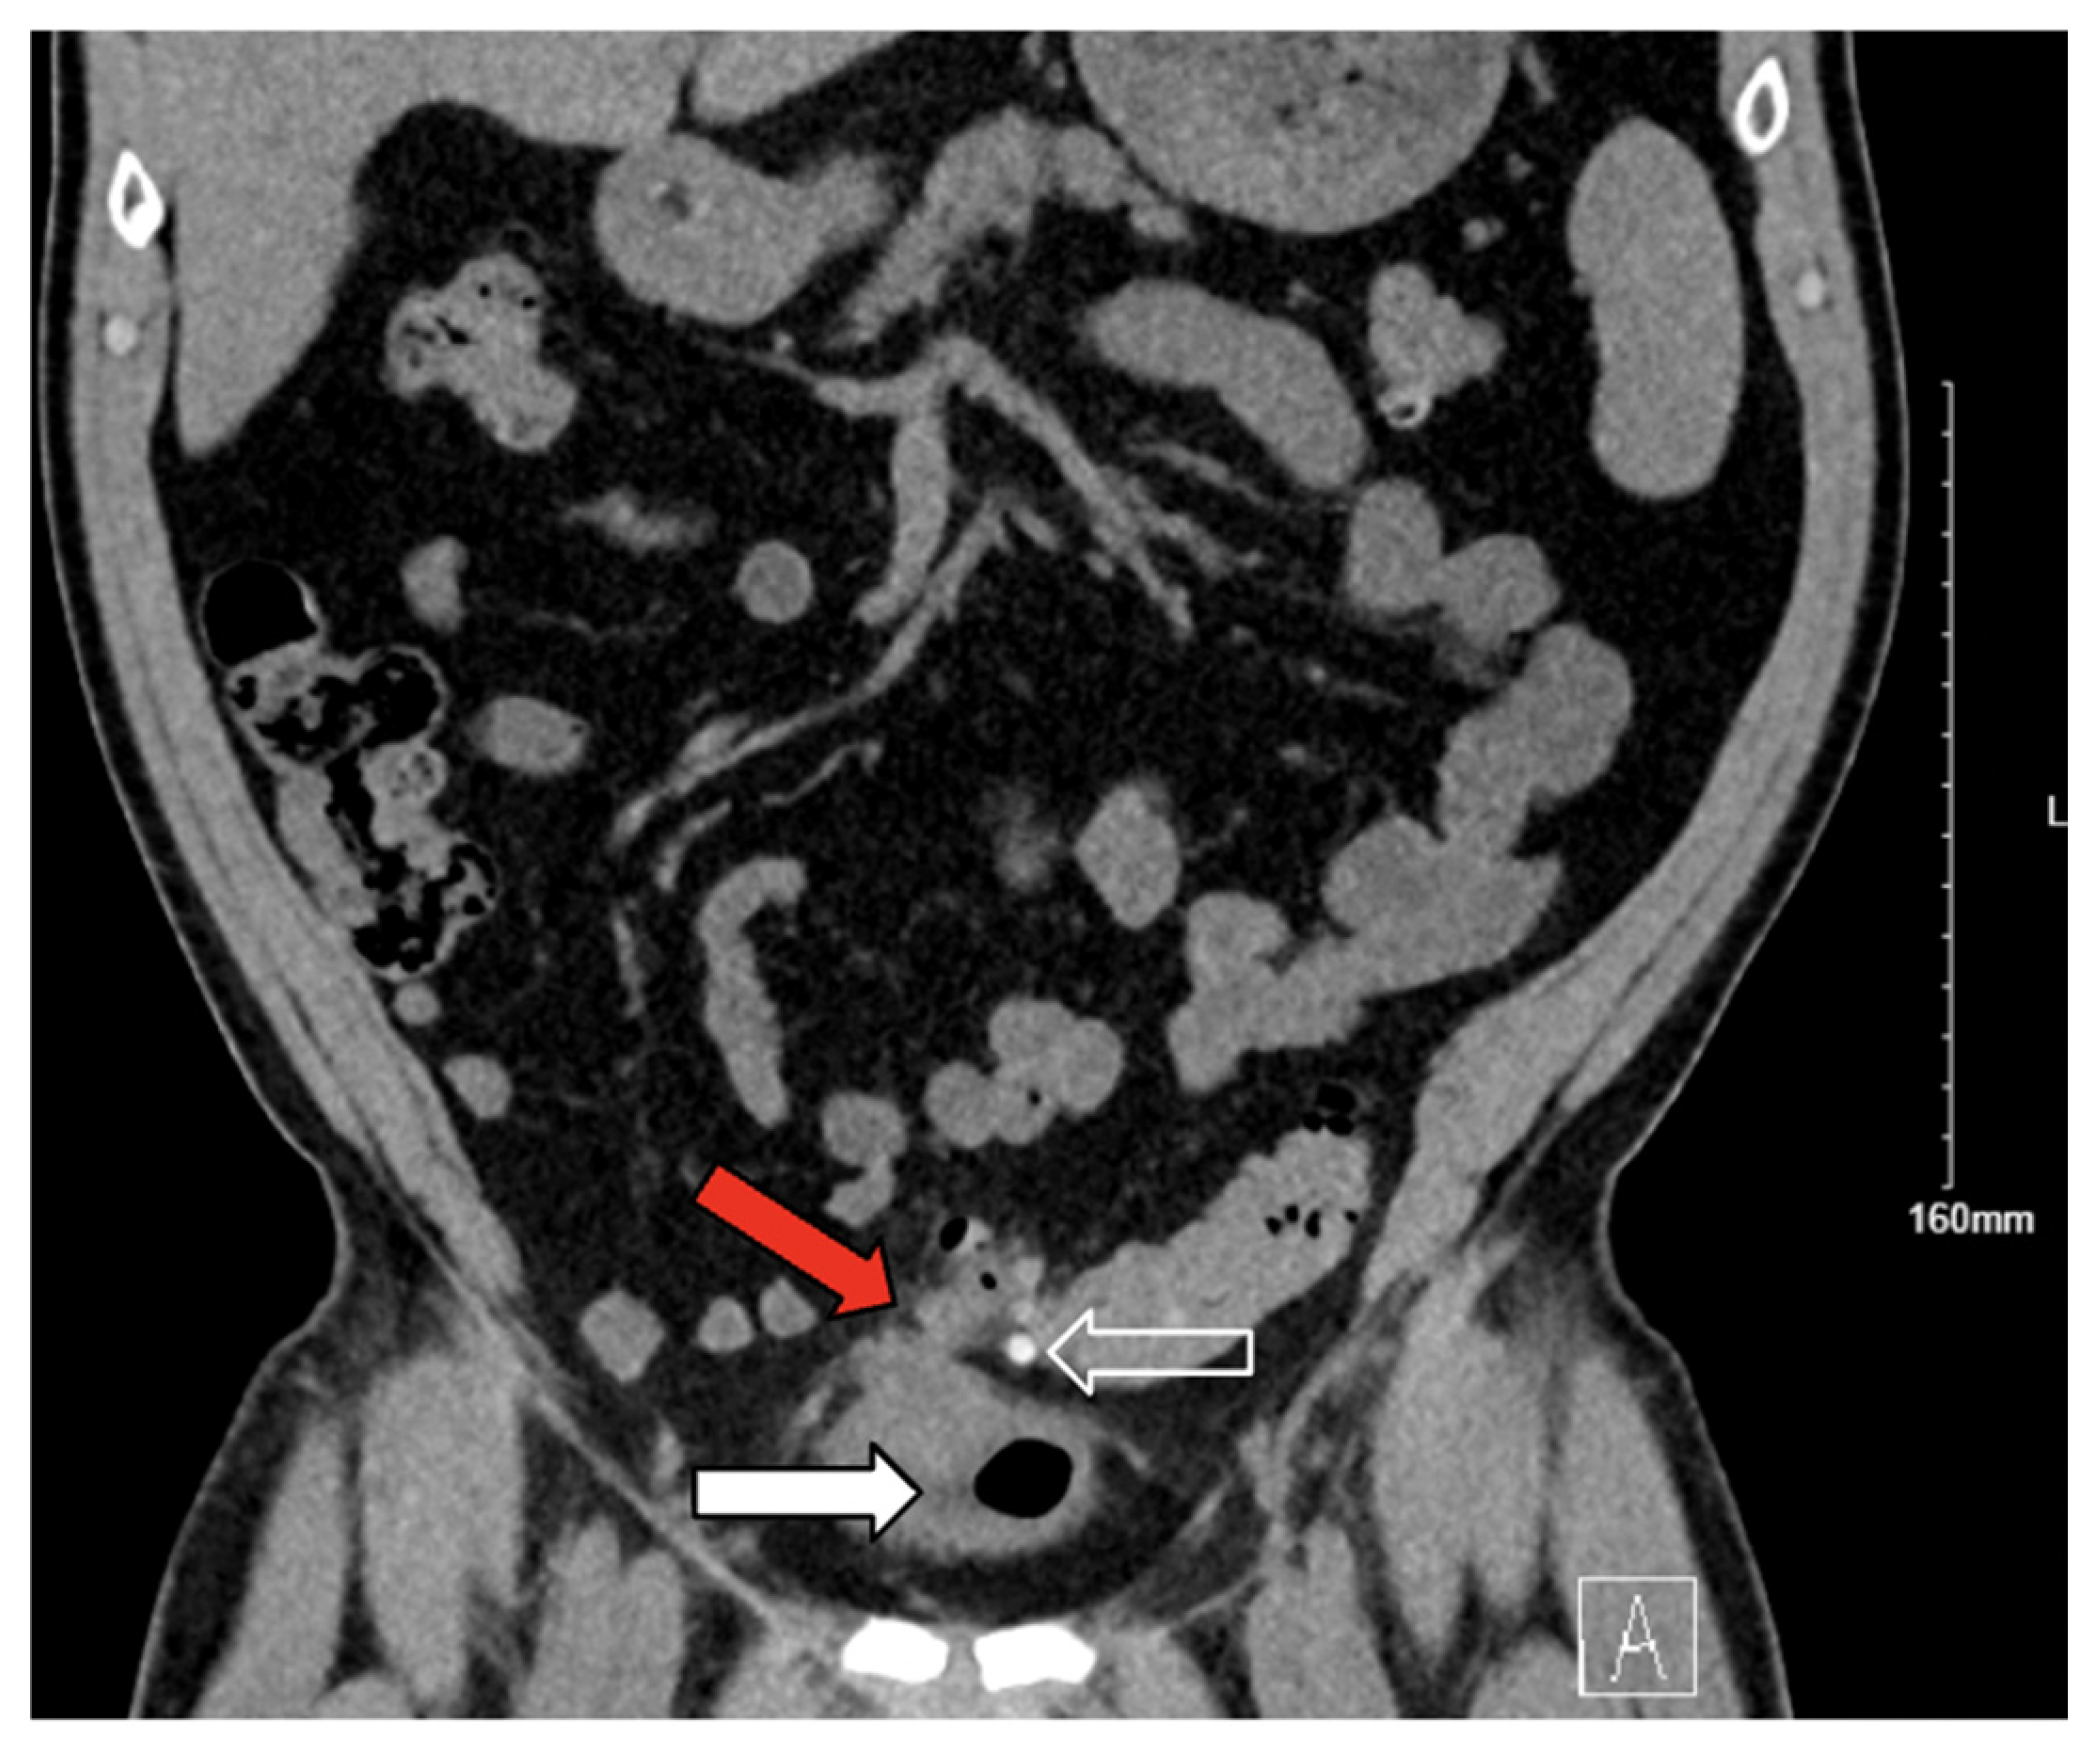

3.2. Case 2